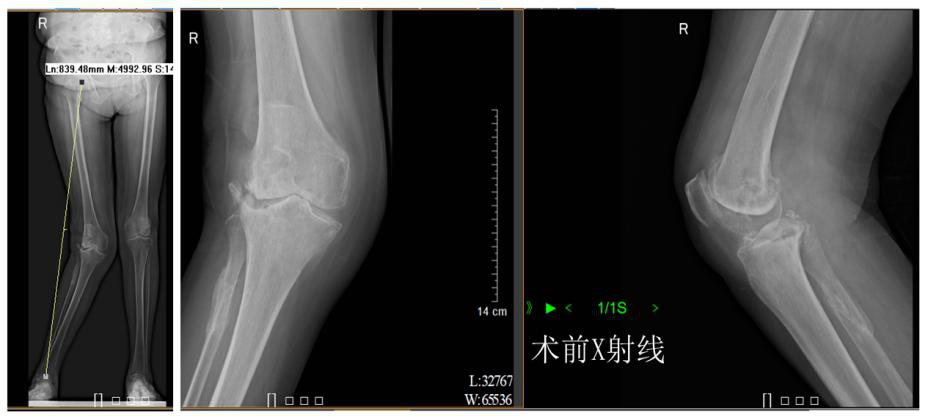

据了解,患者柯姨已经78岁了,20多年前,她的右膝出现反复疼痛的症状,并在10年前开始加重,导致活动困难甚至最后丧失了日常功能。但是,这么多年来柯姨一直讳疾忌医,不肯接受治疗。她的家属经过多方咨询、了解,最后选择来到茂名市人民医院关节四肢骨病外科住院手术治疗。术前X线片显示,柯姨的病症是右膝关节重度骨性关节炎,并重度外翻畸形,外翻角约30°。

术前术后X射线对比

据介绍,利用人工膝关节置换术治疗重度膝关节炎是公认的消除疼痛、矫正畸形、改善功能的有效方法,可以极大提高患者的生活质量。茂名市人民医院关节四肢骨病外科陈关林主任医疗团队经过充分术前讨论,为柯姨制定了合适的治疗方案,在腰硬联合麻下行右侧人工全膝关节置换术。整个手术用时近3小时,最后取得了非常满意的效果。术后,在尤英光护长带领的护理团队精心的护理及专业的康复锻炼下,可以很快就可以下地负重锻炼,并如期出院回家。柯姨及其家属为答谢该科医护人员,特意为他们送上锦旗。